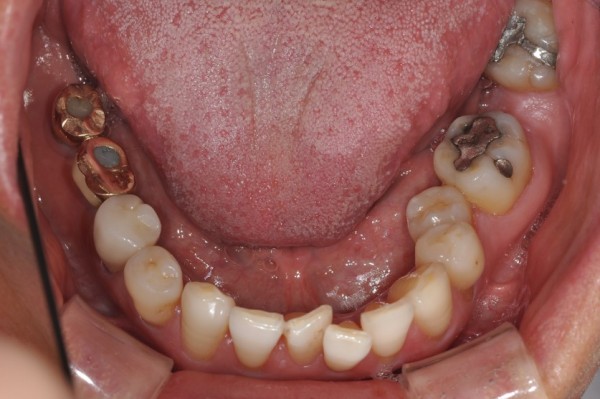

치료 전후사진

Before & After

앞니 부분교정 / 중장년 교정

서울린교정치과

*50대 남성 *아래 앞니만 부분교정 *치료기간: 6개월